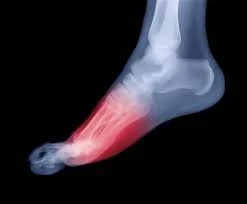

Read MoreCommon Foot Conditions Treated with Orthotics

OrthoCarolina providers can refer patients to Performance Orthotics